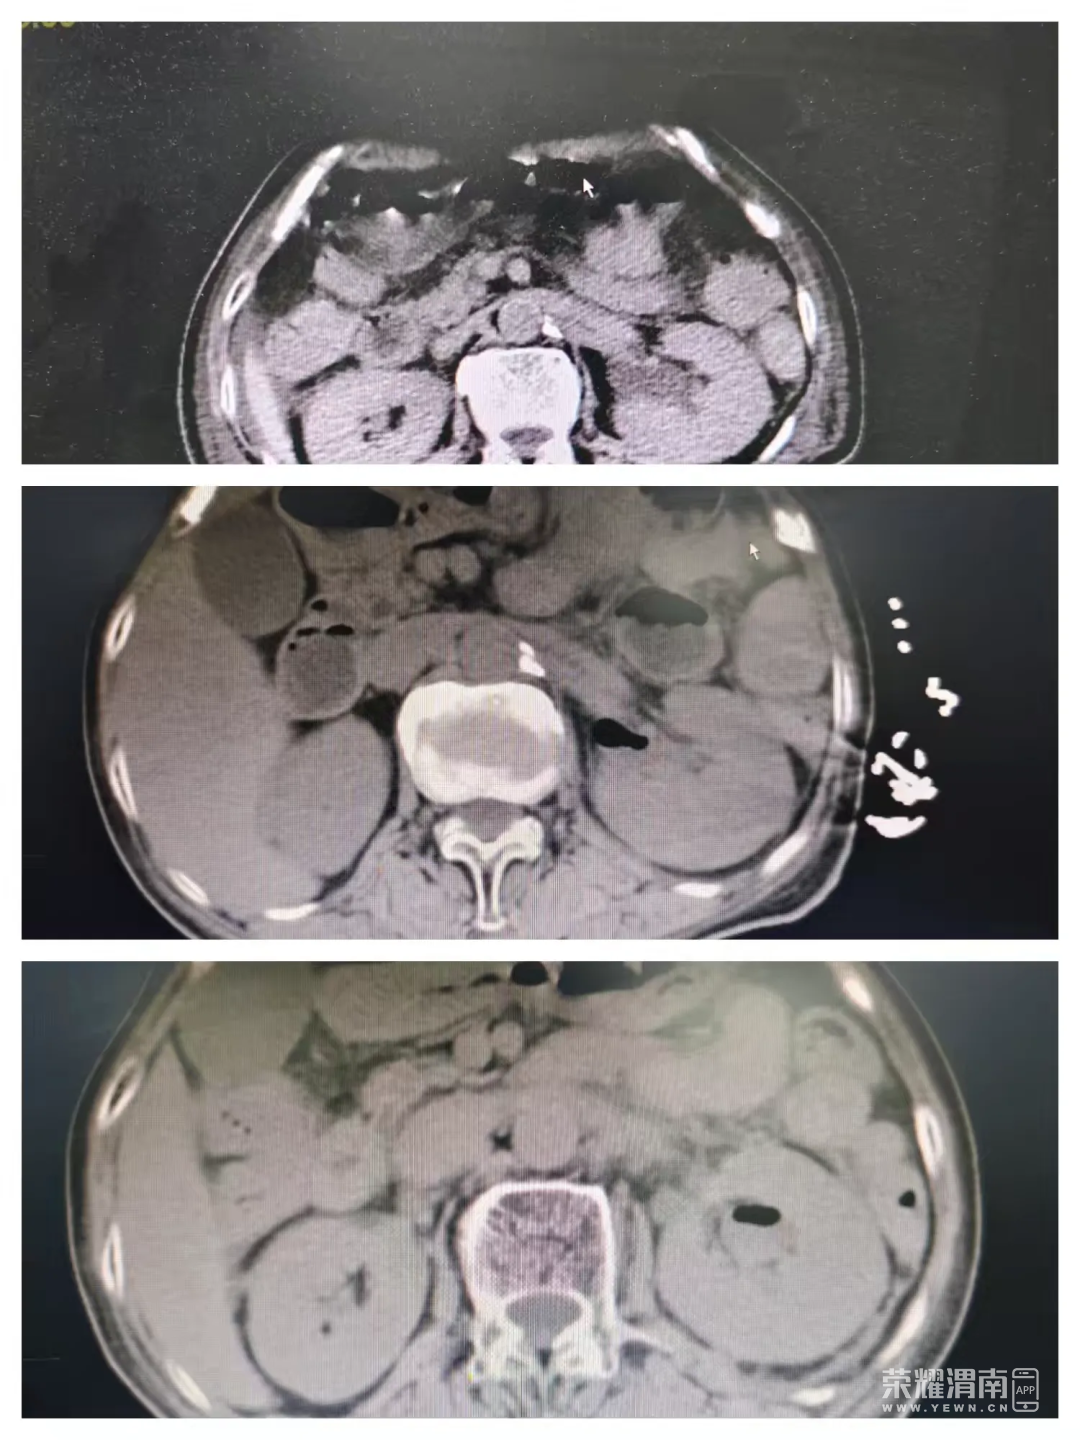

张阿姨有8年多的糖尿病史,长期血糖控制不佳,此次伴有肾区叩击痛及左下腹压痛。全腹CT提示:双肾稍饱满,周围有渗出,左侧肾盂、输尿管及膀胱内可见积气。至此,谜底揭开——她患上了俗称肾脏“生气”的气肿性肾盂肾炎并已引发脓毒性休克、脓毒症性凝血病、急性肾损伤等多种危重并发症。